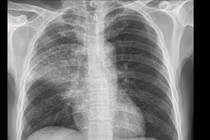

Viêm phổi được biểu hiện bằng viêm phổi thùy, viêm phổi đốm hoặc viêm phổi không điển hình. Đặc điểm chung là có hội chứng đông đặc phổi và bóng mờ phế nang hoặc mô kẽ trên phim X-quang phổi. Bệnh do vi khuẩn, vi rút, nấm và một số tác nhân khác, nhưng không do trực khuẩn lao.

Sự phối hợp đa chuyên khoa đã giúp bệnh nhân hồi phục - Ảnh BVCC